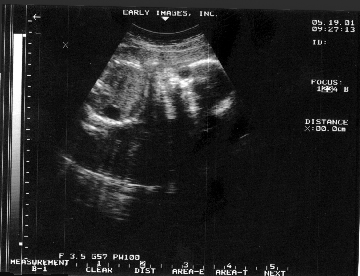

LOOK AT ME IN THE BELLY